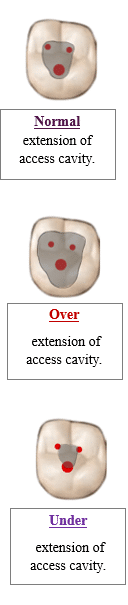

Incorrect shape of access cavity

Over-extension of the access cavity

The access cavity becomes too wide (than necessary) or too deep.

Under-extension of the access cavity

Under-extension of the access cavity occurs when the cavity is too small or shallow.

You fail to properly expose the pulp chamber and root canal orifices.